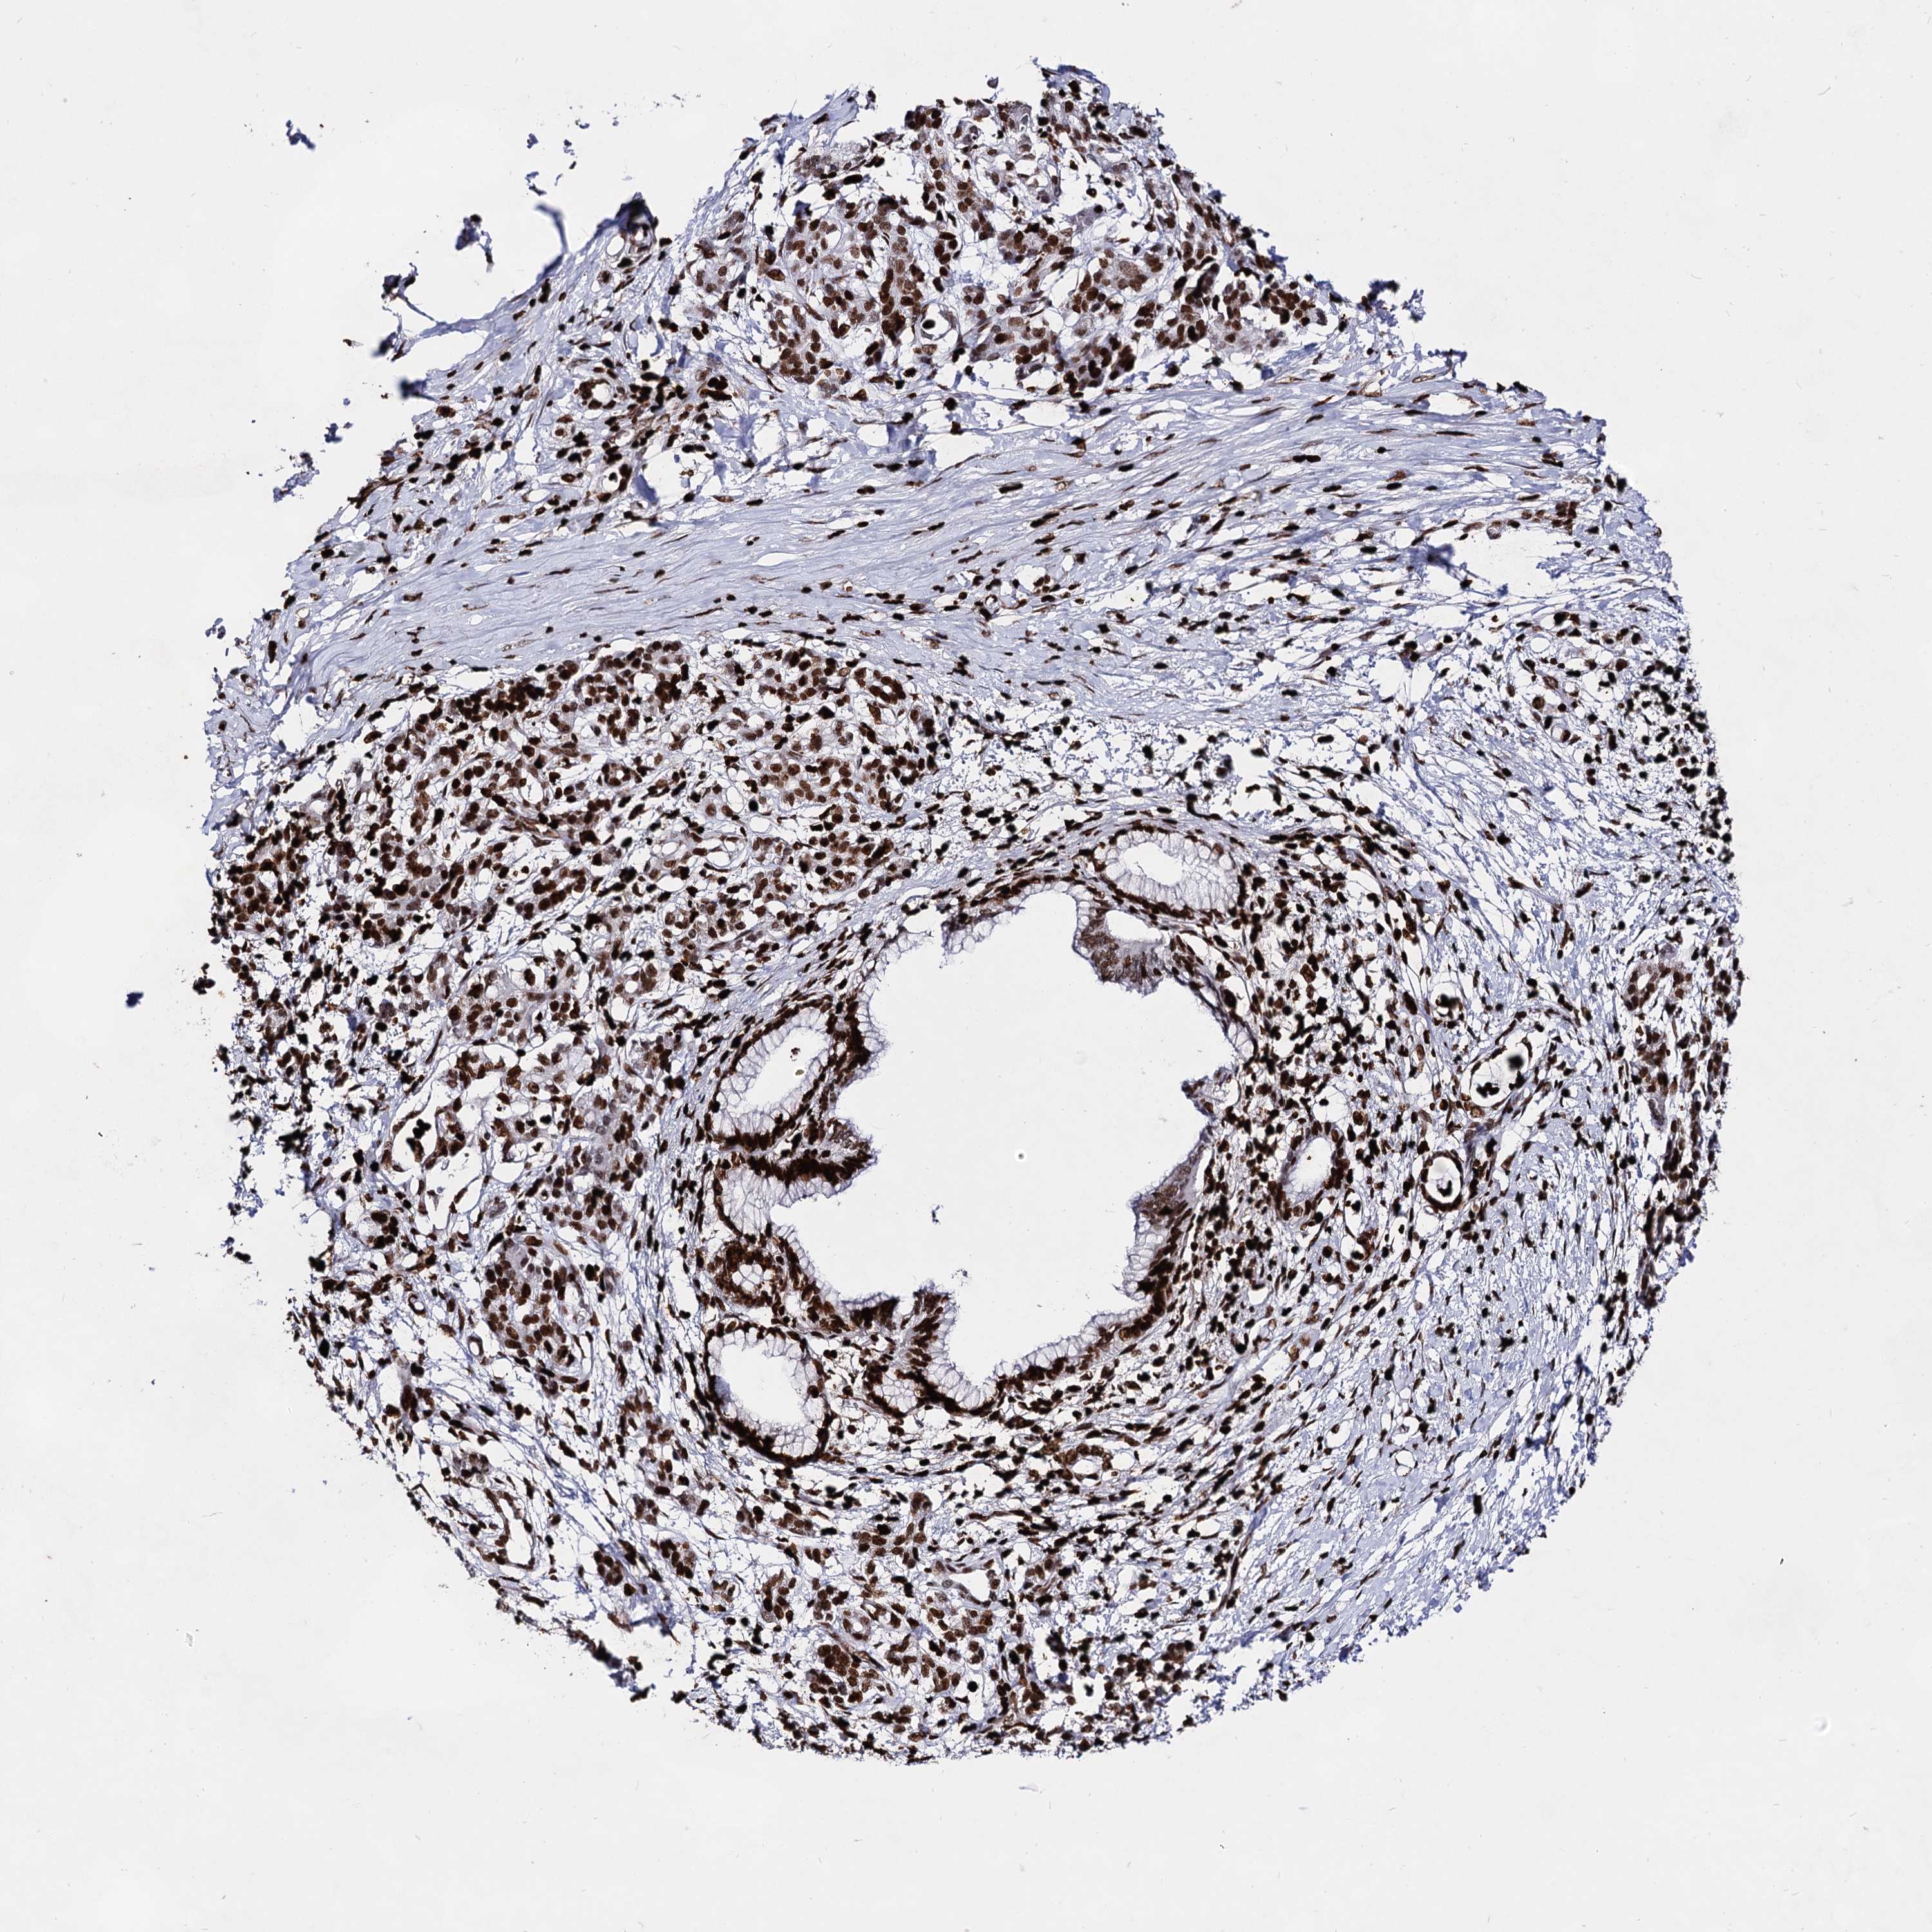

PANCREATIC CANCER - Protein expressioni

A mouse-over function shows sample information and annotation data. Click on an image to view it in a full screen mode. Samples can be filtered based on level of antibody staining by selecting one or several of the following categories: high, medium, low and not detected. The assay and annotation is described here.

Note that samples used for immunohistochemistry by the Human Protein Atlas do not correspond to samples in the TCGA dataset.

Antibody stainingi

Antibody staining in the annotated cell types in the current human tissue is reported as not detected, low, medium, or high, based on conventional immunohistochemistry profiling in selected tissues. This score is based on the combination of the staining intensity and fraction of stained cells.

Each image is clickable and will lead to virtual microscopy that enables deeper exploration of all samples and also displays staining intensity scores, fraction scores and subcellular localization as well as patient and tissue information for each sample.

Antibody HPA003506

Antibody CAB037206

Staining

High

Medium

Low

Not detected

Intensity

Strong

Moderate

Weak

Negative

Quantity

>75%

75%-25%

<25%

None

Location

Nuclear

Cytoplasmic/membranous

Cytoplasmic/membranous,nuclear

Adenocarcinoma, NOS